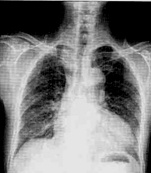

| 病史:男性,65歲,突感胸悶氣促1小時。診斷: |

| ○ 右側(cè)氣胸 | |

| ○ 右側(cè)大葉性肺炎 | |

| ○ 右側(cè)胸腔積液 | |

| ○ 肺結(jié)核 | |

| ○ 右側(cè)肺癌 |